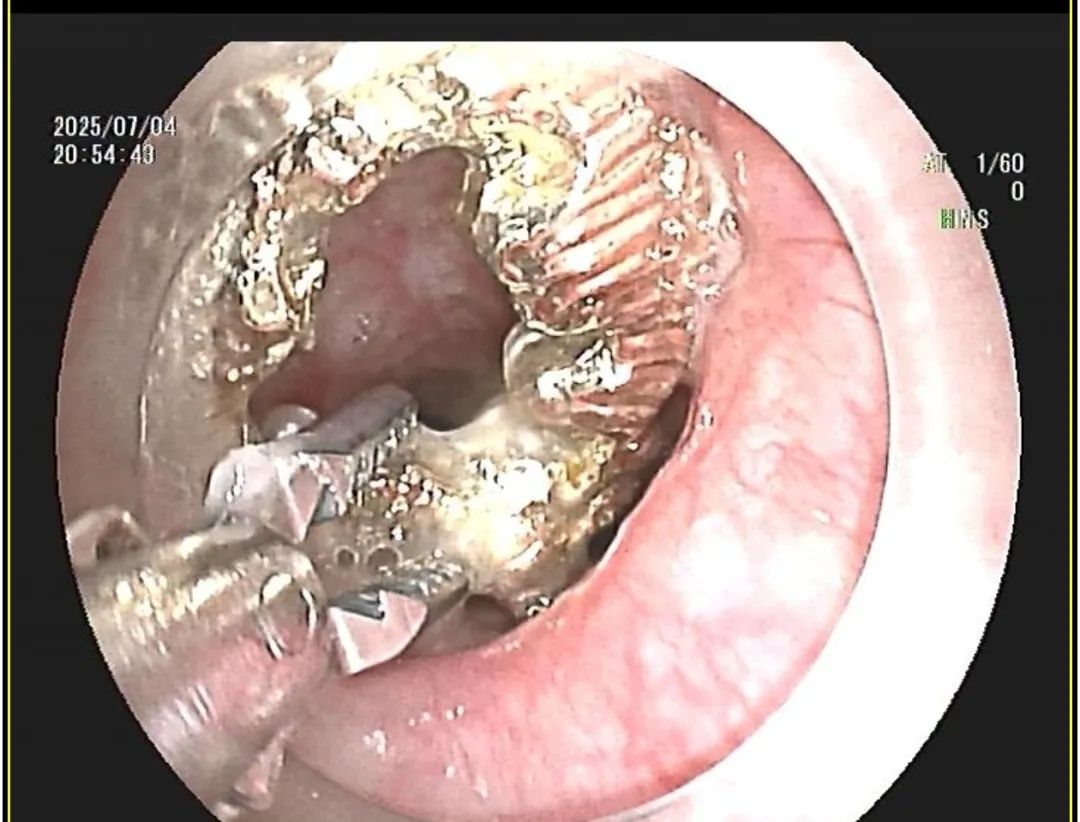

考虑到异物较大且材质坚硬,消化内科团队迅速决定采用无痛胃镜技术进行紧急取出。在麻醉科配合下,手术顺利进行。医生通过胃镜精准定位异物,并使用专用器械,小心地将耳环从女童胃内完整取出。术后,女童恢复良好,未造成消化道损伤。